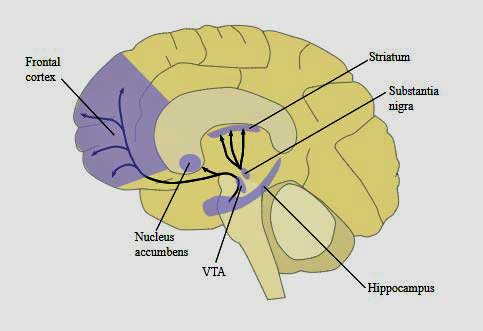

The substantia nigra is part of the basal ganglia – a set of structures in the midbrain which affect “reward”, fatigue and movement. Damage to one part of the substantia nigra is responsible for the movement problems in Parkinson’s disease. Without the substantia nigra, we couldn’t (subconsciously) “plan” movement – an essential part of being able to move at all.

Notice the concentration of dopamine in the midbrain (basal ganglia and hippocampus) and the prefrontal cortex. The Japanese believe dopamine reductions in these areas are producing fatigue in ME/CFS

After studies suggested that this “sickness behavior” is being produced by the basal ganglia in hepatitis C, Miller used a functional MRI (fMRI) to measure the basal ganglia’s response to “reward” in ME/CFS patients and healthy controls.

Miller used “reward” because hepatitis C studies have shown that “reward” is strongly associated with fatigue, our mood and, interestingly, how well we move and react. In that vein, it’s interesting that ‘psychomotor’ slowing – one of the most consistent findings in ME/CFS – is also commonly found in people with basal ganglia dysfunction – and is also highly associated with fatigue severity.

Miller found that mental and physical fatigue and reduced activity in ME/CFS was correlated with reduced activation of the globus pallidus (GP) in the basal ganglia (BG). Reduced input from the striatum in the basal ganglia was also found.

That reduced input, Miller thought, was probably indicative of an under-functioning dopamine system. In fact, Miller suggested that problems with reduced dopamine functioning might be found across the brain in ME/CFS.

Dopamine plays a pivotal role in the regulation of mood, motivation, reward, motor activity (movement), and sleep-wake cycles. Low levels of dopamine can result in high levels of effort being needed for even simple tasks.

Other researchers are hovering around this area. Japanese researchers have proposed that an inhibited circuit involving the prefrontal cortex, the basal ganglia and other structures stops signals going to the motor cortex to increase muscle performance.

Miller also highlighted dopamine – a hormone/neurotransmitter – which plays a critical role in reward, motor activity (movement), sleep and wakefulness, mood and possibly pain. Low dopamine levels can make even small activities fatiguing.